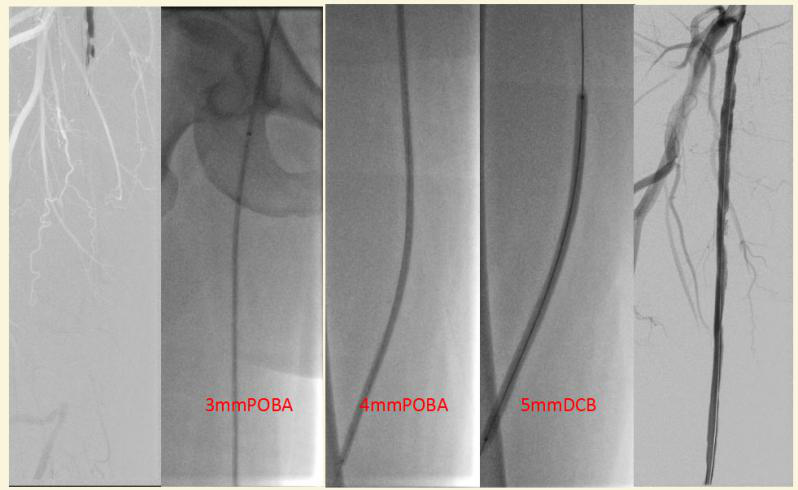

药涂球囊治疗糖尿病性血管病变

其次,引进先进技术理念,专注开通血管。导致“糖足”的罪魁回首是下肢动脉硬化闭塞,目前的主流治疗方式就是微创的血管腔内治疗,通过球囊扩张、放置支架治疗病变,而腔内治疗后再狭窄是高发的问题,特别是合并糖尿病的动脉硬化闭塞,一般有严重的钙化,血管闭塞很严重,特别是如大腿根部一下的动脉尤其纤细,一般的球囊扩张很难扩张充分,即使植入支架由于斑块负荷过大,也容易再次狭窄,严重时就会截趾、截肢甚至溃疡感染危及生命。清华长庚医院血管外科积极引入先进腔内治疗理念及技术,包括药涂球囊(Drug-coatedballoon,DCB),斑块切除或减容、血栓抽吸、巧克力球囊、药涂支架等,承担了多项全国多中心临床试验,并在国内核心期刊发表《药物涂层球囊治疗股腘动脉长段病变的中远期结果及其预后因素》、《重视营养不良对慢性肢体威胁性缺血的影响》、《镍钛合金约束球囊导管腔内治疗下肢动脉粥样硬化闭塞症的临床结果》等腔内治疗的论文。